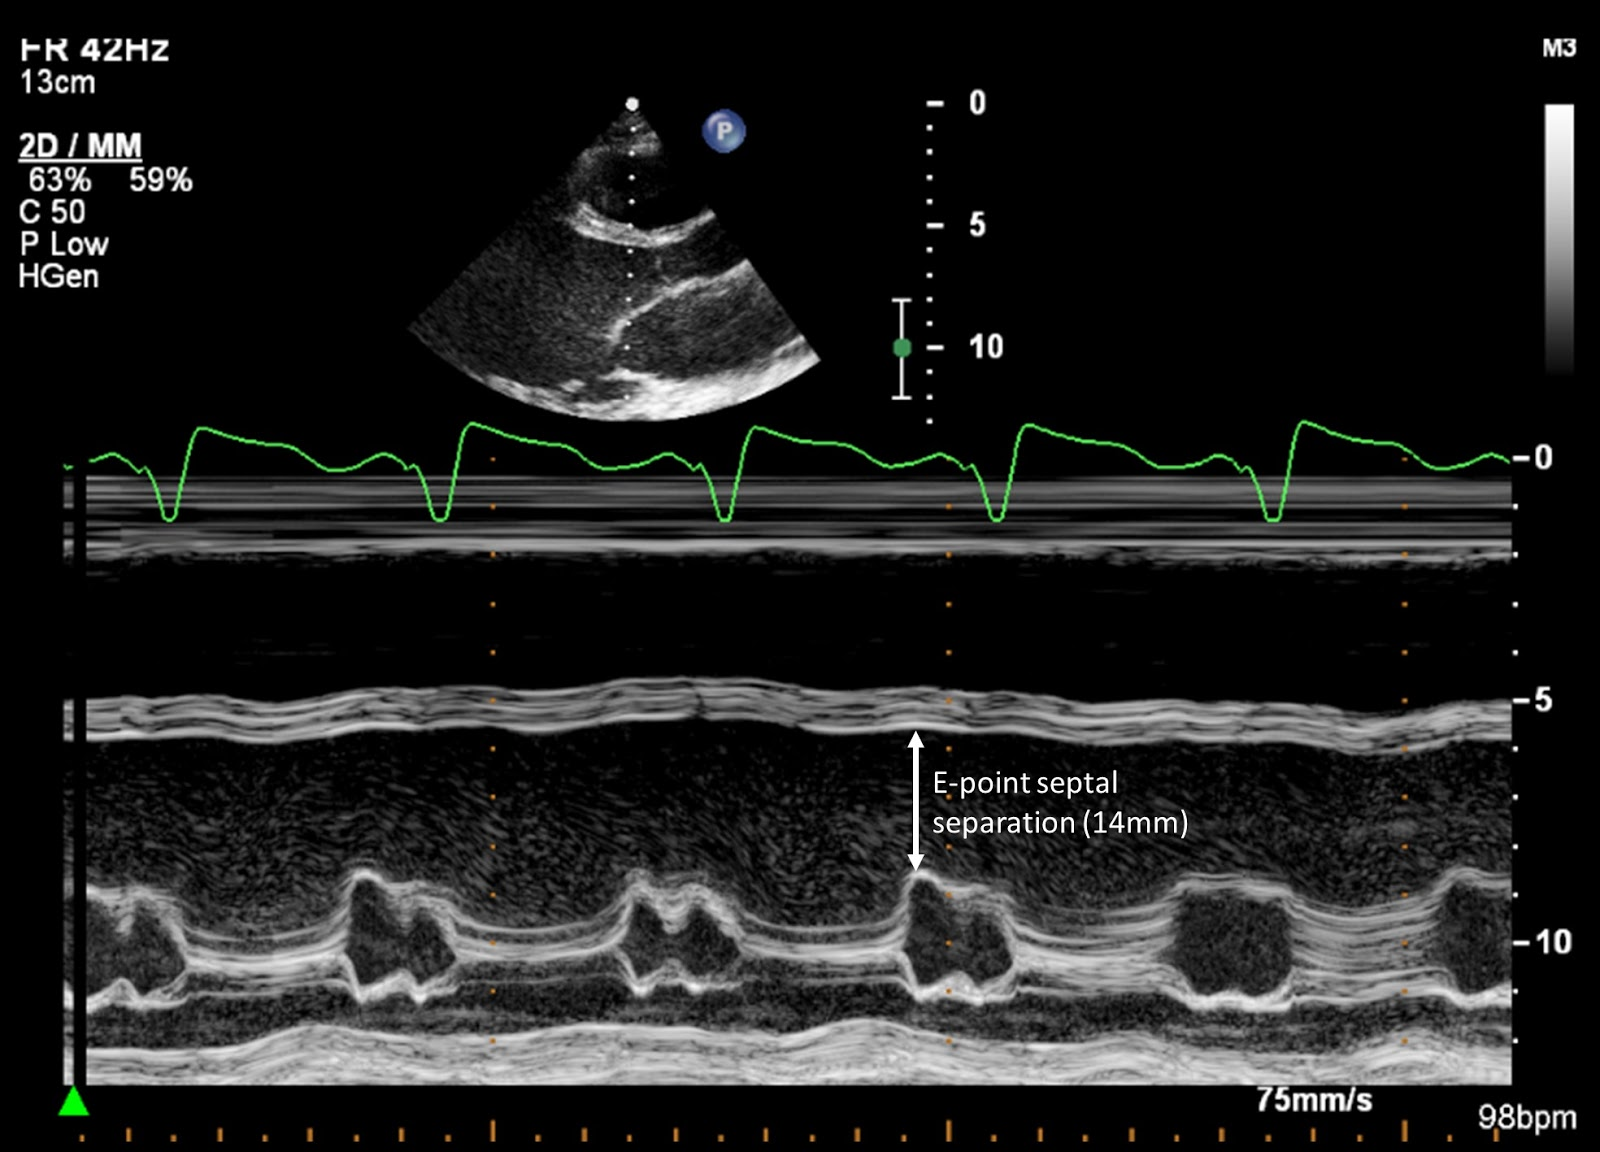

Increased e point septal separation

What m-mode finding is seen on both aortic insufficiency and DCM?

Dilated CM w/ MS

What does this m-mode image show?